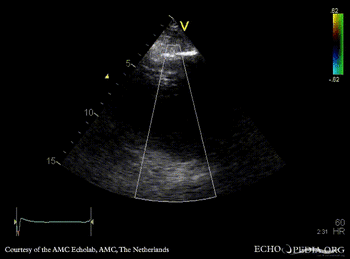

| A4CH: coronary fistula | Pulsed-wave signal of flow through coronary fistula |